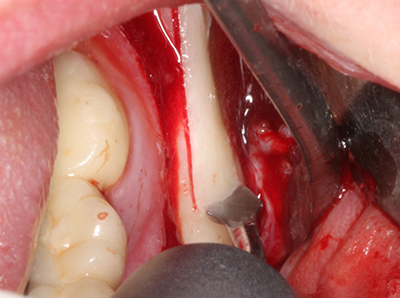

Fig. 3: La separación basal del bloque se ve facilitada con piezas dotadas de una angulación especial.

Fig. 4: Con la rasqueta ósea se obtienen virutas adicionales de hueso autógeno.

En la extracción de bloques óseos la piezocirugía también presenta ventajas adicionales: Además de la alta precisión en la osteotomía que ya se ha descrito antes, se ha comprobado que el uso de los delgados insertos de sierra resulta especialmente cuidadosas con el hueso. Frente a esto, sobre todo cuando se usan las fresas de Lindemann, cabe esperar pérdidas en la extracción significativamente más altas debido al mayor grosor de la parte frontal del cabezal (Lakshmiganthan, Gokulanathan et al. 2012). La separación basal que se necesita en particular en los injertos de bloque extraídos de forma retromolar se ve facilitada mediante sierras perpendiculares especialmente previstas a tal fin, lo que permite considerar que la cirugía piezoeléctrica es un procedimiento preciso y seguro para la obtención de bloques de hueso en el área retromolar (Happe 2007) (fig. 1-12).